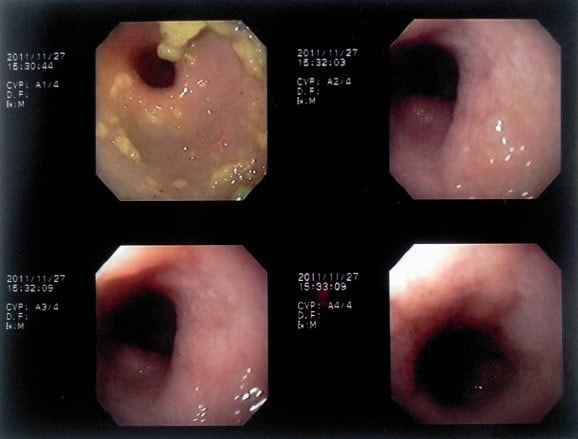

症例:炎症性ポリープ M.ダックス 10歳 オス

主訴:8ヶ月前から便が細くなり、血が混じることがある。その他、元気・食欲等、一般状態は良好。

経過:超音波検査にて直腸壁の肥厚(5㎜)が認められた。また、直腸検査で直腸全周に結節状病変を触知し、出血も確認された。消炎剤、抗生剤、整腸剤による治療への反応が長期的に悪いため、生検も含めた内視鏡検査を実施した。

内視鏡検査:肛門付近の直腸全周に、炎症および出血を伴う結節状病変を多数認めた。

病理検査:直腸の病変は、良性の非腫瘍性病変の一つである“炎症性ポリープ”と診断された。

診断後経過:炎症性ポリープは多発する傾向や腫瘍に転化する可能性があるため、消炎剤、抗生剤、整腸剤による内科療法を継続しながら、現在プルスルー法による外科的摘出術を検討中。